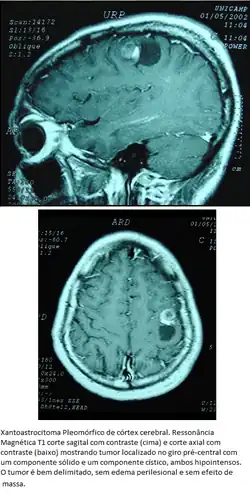

Xantoastrocitoma Pleomórfico

Tumor astrocitário raro, de crianças e adultos jovens, com localização superficial nos hemisférios cerebrais, envolvimento das meninges e prognóstico favorável. Tem aspecto pleomórfico, incluindo células tumorais lipidizadas que expressam GFAP (portanto, de linhagem astrocitária), que pode estar envolvidas por estroma reticulínico. Em relação à invasão de estruturas cerebrais, ocupam posição intermediária entre os astrocitomas pilocíticos e os difusos. Contudo, podem ter feições histológicas agressivas.

Localização. Preferência pelo lobo temporal. O tumor é cortical, estendendo-se da leptomeninge à transição com a substância branca. As bordas são nítidas em TC e RM, com tendência à formação de cistos com nódulo mural. Há captação de contraste.

Morfologia. São aderidos às leptomeninges. Há componentes sólido e cístico. O nódulo mural é amarelo-alaranjado e mais firme que o cérebro. Microscopicamente, observam-se astrócitos pleomórficos gigantes, mono- ou multinucleados, com grande variação no tamanho e cromatismo dos núcleos (daí o adjetivo pleomórfico) misturados a células pequenas, poligonais ou fusiformes, GFAP-positivas e arranjadas em fascículos. O termo xantoastrocitoma é devido a que muitas células, especialmente as maiores, mostram acúmulo de gotículas lipídicas. A celularidade é moderada, mas pode ser focalmente alta. Mitoses e necrose são raras ou ausentes. Embora o tumor apareça macroscopicamente bem delimitado, pode haver invasão do cérebro e de espaços perivasculares. Em impregnações pela prata, fibras reticulínicas podem ser abundantes e circundar individualmente células tumorais. Em microscopia eletrônica, as células são envoltas por membrana basal, uma feição também encontrada em astrócitos subpiais normais. Por isto, foi postulada origem nestes. A consistência firme é atribuída ao estroma reticulínico, mais proeminente onde há envolvimento leptomeníngeo.